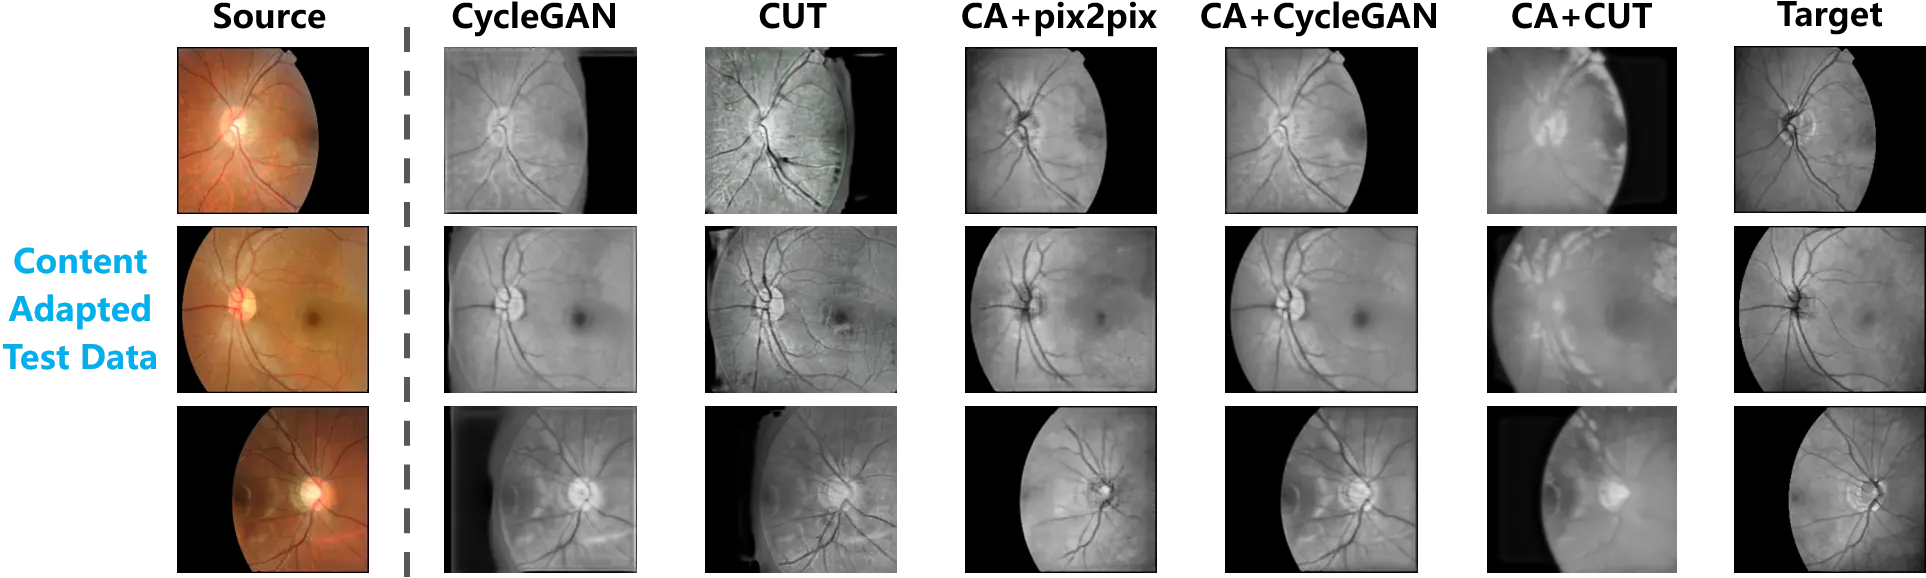

3.2.2 Evaluation with content adapted data

To further investigate the influence of training samples, the test data that underwent content adaptation was also used for the evaluation. Figure 6 exhibits the synthesized outputs based on the content adapted test data. In the first and last columns, the source and target samples are respectively presented.

Figure 6. The cross-modality translation tested on the content adapted retinal data. The paired test data are provided by content adaptation. A comparison between the translation outputs and the target samples is thus presented.

Consistent with the observation in Figure 5, the translation mapping learned from the original data still tried to fill the background of the source samples, while the foreground and background in the source samples were satisfactorily preserved by the models trained on the content adapted data.

Following the above-mentioned evaluation, Table 2 summarizes the quantitative measurement of hallucination. PA and MIoU were computed from the content adapted test data. According to the quantitative comparison between the models trained on the original and content adapted data, significant progress can be observed.

Based on the comprehensive evaluation of Figure 5 and Figure 6, as well as Table 1 and Table 2, unbiased training data is critical to correctly learn the translation mappings from the source to the target domain. Because of the distribution bias, the real shift between the source and target domains was distorted, and as a result of this distortion, the translation models made efforts to import the bias into the source samples during the training stage, with the purpose of matching the target domain. In this experiment, the distribution bias of the foreground in the original training data led the translation models to attempt to synthesize data of the target domain by filling the background. Therefore, no matter whether the original data or the content adapted data was employed in the test, hallucination appeared in the synthesized images.

Content adaptation helps to align the source and target samples, which constrains the distribution bias. The aligned training samples allow the translation models to properly estimate the domain shift and learn a mapping from the source to the target domain. Accordingly, the mappings learned from the content adapted data were immune to the distribution bias of the foreground. They did not fill the background in the source samples with hallucinations. Moreover, the mappings correctly learned from content adapted data were robust with respect to the test data, since hallucination was equally limited on the original test data.